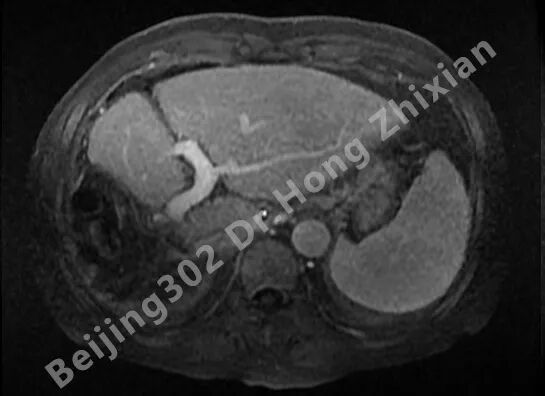

临床随笔丨肝癌术前新辅助治疗:“更优选择”还是“过度治疗”?

病例简介